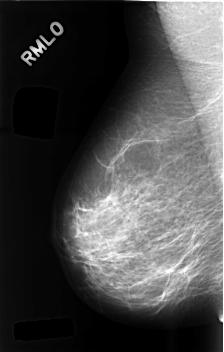

C_0489_1.RIGHT_MLO

RIGHT_CC LINES 4576 PIXELS_PER_LINE 2944 BITS_PER_PIXEL 12 RESOLUTION 50 NON_OVERLAY

RIGHT_MLO LINES 4576 PIXELS_PER_LINE 2912 BITS_PER_PIXEL 12 RESOLUTION 50 NON_OVERLAY